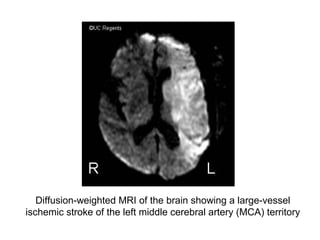

Diffusion-weighted MRI of the brain showing a large-vessel

ischemic stroke of the left middle cerebral artery (MCA) territory

Diffusion-weighted MRI ofthe brain showing a large-vessel ischemic stroke of the left middle cerebral artery (MCA) territory